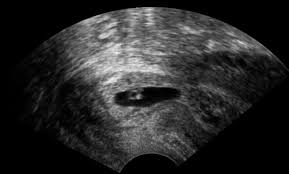

Cervix In Early Pregnancy Pictures, Cervix Position In Early Pregnancy How To Check For Cervical Position And What You Should Know - Jun 23, 2020 · with early pregnancy, the position of the cervix rises back, but it will not go as far back as it was before pregnancy.. It remains hard until weeks before the delivery. The changes in the cervix's texture and position are the first things that happen after the fertilization is done. Eventually, the cervix will start dilating and the mucus plug will be lost. The cervix during early pregnancy is hard, but at the same time, it stays high. In some women, these changes can occur weeks before delivery.

Pregnancy causes higher levels of estrogen, leading the body to produce more discharge and increase the. The cervix during early pregnancy is hard, but at the same time, it stays high. The changes in the cervix's texture and position are the first things that happen after the fertilization is done. Your mucus plug will prepare itself for pregnancy. Closed during early pregnancy and it is located very far back in the vaginal vault. The early changes that signify pregnancy become present in the first trimester. Can cervix be high and firm in early pregnancy? Female reproductive system with labels anatomy. It remains hard until weeks before the delivery. Learn about pregnancy · hope and support · women just like you Sep 14, 2020 · soft cervix in early pregnancy. The ideal time for conception during ovulation is when the cervix is high, soft and open. Dec 21, 2020 · early in a pregnancy, a person might experience a slight increase in vaginal discharge.

The ideal time for conception during ovulation is when the cervix is high, soft and open. Need advice, support and resources? How does the cervix change during early pregnancy? Jun 15, 2019 · cervix position during conception and early pregnancy. What if your cervix is open during early pregnancy? Mucous is usually thin and colourless. Once you have conceived, early pregnancy will make your cervix high, soft and closed. Pregnancy causes higher levels of estrogen, leading the body to produce more discharge and increase the.